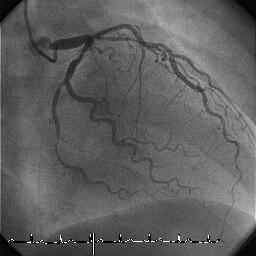

8/28にちょっと書いたLMT bifurcationの画像を提示したいと思います。66歳の男性

で、HT/DM/HL/smoking/obesity/FHとすべてそろっています。

Fig1 PCI前です。IABPが入っており、ガイドカテは8Fr Joガイド JCL4です。

LMT-LADは99%delay、LMT-LCxは90%と読みました。

Fig.1